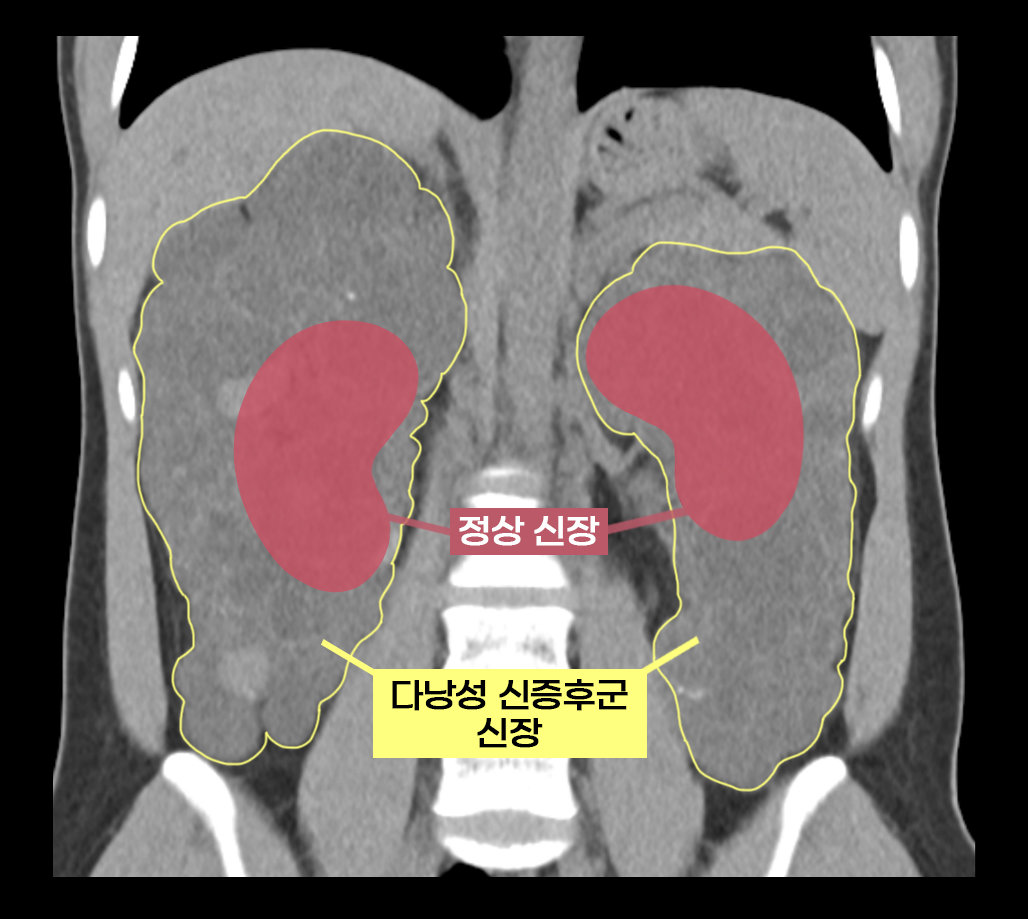

서울아산병원 의료진이 다낭성 신증후군으로 신장이 7배나 커진 환자에게 로봇을 이용하여 비대해진 신장을 안전하게 제거하고 공여자의 건강한 신장을 이식하는 데 성공했다. 이는 아시아 최초, 전 세계 3번째 사례다.

30일 서울아산병원은 신췌장이식외과 신성, 김진명 교수팀이 16일 다낭성 신장증후군으로 인한 신장 비대로 만성신부전을 앓던 이가영 씨(24)에게 로봇 신장이식을 했다고 밝혔다. 이 씨는 신장에 셀 수없이 많은 낭종이 발생해 신장이 최대 축구공만큼 커지는 유전 질환인 다낭성 신증후군을 앓았다. 1000명 중 1명 꼴로 비교적 흔하게 발생하며 대부분 만성 신부전으로 이어진다.

보통 만성 신부전 환자는 신장이식 시 기존 신장을 그대로 두지만, 다낭성 신증후군은 기존 신장을 떼 내야 한다. 기존 신장이 비대해진 상태라 새 신장이 들어올 공간을 확보하고, 감염, 출혈 등의 위험성을 줄이기 위해서다.